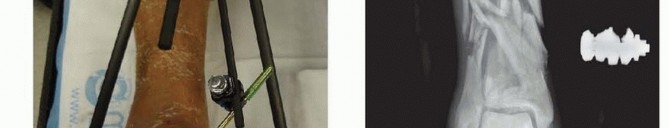

Indications for external fixation of the tibial shaft in trauma applications include the treatment of open fractures with extensive soft tissue devitalization and contamination. Other indications include the stabilization of closed fractures with high-grade soft tissue injury or compartment syndrome. External fixation is favored when the fracture configuration extends into the metaphyseal/diaphyseal junction or the joint itself, making other treatment options problematic. For patients with multiple long bone fractures, external fixation has been used as a method for temporary, if not definitive, stabilization. 3 With the introduction of circular and hybrid techniques, indications have been expanded to include the definitive treatment of complex periarticular injuries, which include high-energy tibial plateau and distal tibial pilon fractures. 4 Hexapod fixators can be used to perform gradual reductions of the tibial shaft or periarticular injuries in cases of severe soft tissue injury where soft tissue coverage procedures are contraindicated and in cases of delayed presentation where acute distraction and reduction would compromise neurovascular elements 12 ( FIG 1F). ### FIG 1 • A. Simple monolateral four-pin frame with a double-stack connecting bar to increase frame stability. B. X-ray demonstrating ability to connect the fixation pins to each limb segment in a variety of ways to achieve a congruent reduction. C. Large monotube fixator spanning the ankle for a severe pilon fracture. This was applied to temporize the soft tissues before definitive open stabilization of the injury.

Contemporary external fixation systems in current clinical use can be categorized according to the type of bone anchorage used. Fixation is achieved either using large threaded pins, which are screwed into the bone, or by drilling smalldiameter transfixion wires through the bone. The pins or wires are then connected to one another through the use of longitudinal bars or circular rings. The distinction is thus between monolateral external fixation (longitudinal connecting pins to bars) and circular external fixation (wires and/or pins connecting to rings). Acute trauma applications primarily use monolateral frame configurations and are the focus of techniques described here. The first type of monolateral frame is modular with individual components: separate bars, attachable pin-bar clamps, bar-to-bar clamps, and Schanz pins ( FIG 1A,B). These “simple monolateral” frames allow for a wide range of flexibility with “build-up” or “build-down” capabilities. 531

### FIG 1 •

D,E. Small tensioned wire circular fixator used for definitive management of a distal tibial periarticular fracture with proximal shaft extension. The versatility of these frames allows for spanning into the foot to maintain a plantigrade position. F. A hexapod frame attached to the bone with large Schanz pins. This frame allows for gradual correction of fracture displacement over time by adjusting the six distractors. The second type of monolateral frame is a more constrained type of fixator that comes preassembled with a multipin clamp at each end of a long rigid tubular body. The telescoping tube allows for axial compression or distraction of this so-called monotube-type fixator ( FIG 1C). For diaphyseal injuries, the most common type of fixator application is the monolateral frame using large pins for skeletal stabilization. Simple monolateral fixators have the distinct advantage of allowing individual pins to be placed at different angles and varying obliquities while still connecting to the bar. This is helpful when altering the pin position to avoid areas of soft tissue compromise (ie, open wounds or severe contusion). 9 The advantage of the monotube-type fixator is its simplicity. Pin placement is predetermined by the multipin clamps. Loosening the universal articulations between the body and the clamps allows these frames to be easily manipulated to reduce a fracture. Many high-energy fractures involve the metaphyseal regions, and transfixion techniques using small tensioned wires are ideally suited to this region. They have better mechanical stability and longevity than traditional half-pin techniques. Small tensioned wire circular frames or hybrid frames (frames using a combination of large half-pins and transfixion wires) can be useful in patients with severe tibial metaphyseal injuries that occur in concert with other conditions such as soft tissue compromise or compartment syndrome or in patients with multiple injuries ( FIG 1D,E). 532 Hexapod fixators are ring fixators consisting of six distractors and 12 ball joints which allow for 6 degrees of freedom of bone fragment displacement. By adjusting the simple distractors, gradual three-dimensional corrections or acute reductions are possible without the need for complicated frame mechanisms ( FIG 1F).